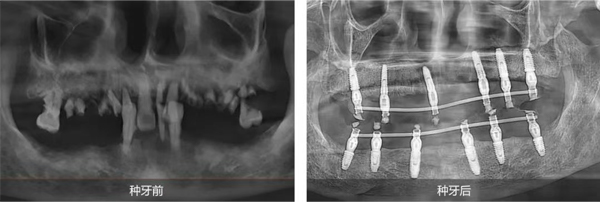

姜辰主任醫(yī)療團隊為陳叔叔定制了全口即刻種植修復(fù)方案。該方案既能滿足陳叔叔盡快恢復(fù)咀嚼功能的需求,又最大程度地減輕了他的痛苦,縮短了治療周期。手術(shù)在陳叔叔家人的陪伴下順利結(jié)束,當天,陳叔叔就戴上了臨時牙冠,恢復(fù)了基礎(chǔ)飲食功能。